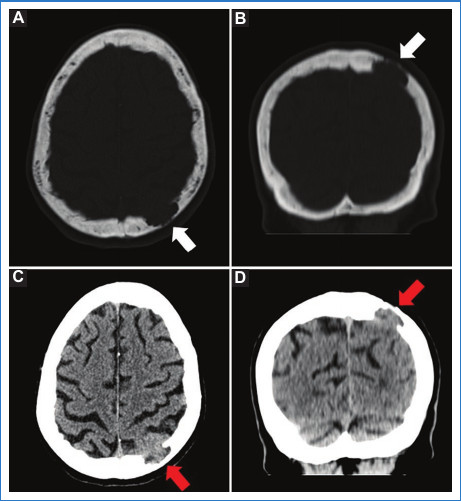

A continuación, presentamos el caso de un paciente de 75 años que consulta por inestabilidad de dos años de evolución, sin presencia de alteraciones cognitivas, cefalea, náuseas, vómitos ni fiebre. La exploración neurológica y analítica no mostró alteraciones significativas. La TC craneal reveló una lesión lítica de bordes bien definidos de aproximadamente dos cm, que causaba lisis total de la tabla interna y en menor medida de la tabla externa del hueso parietal izquierdo (Fig. 1). Dicha lesión se encontraba ocupada por contenido de densidad intermedia en continuidad con el parénquima cerebral subyacente, siendo sugestivo de herniación encefálica (Fig. 1). Se decidió complementar los estudios con la realización de una RM cerebral y una gammagrafía ósea con 99mTc-metil-difosfonato. En la RM se objetivó la ocupación del área lítica por LCR, meninges y herniación del parénquima cerebral, que en la secuencia potenciada en T2 mostraba pequeñas hiperintensidades de señal secundarias a gliosis (Fig. 2). En la gammagrafía no se identificó depósito patológico de radiofármaco en la lesión parietal izquierda ni a ningún otro nivel óseo. Ante la falta de signos de malignidad de la lesión, se determinó como una GAG con herniación del tejido cerebral. La realización de una punción lumbar descartó la existencia de hipertensión secundaria a una posible obstrucción del drenaje venoso, estableciéndose el diagnóstico de GAG como un hallazgo incidental y sin relación con la clínica de inestabilidad referida por el paciente.